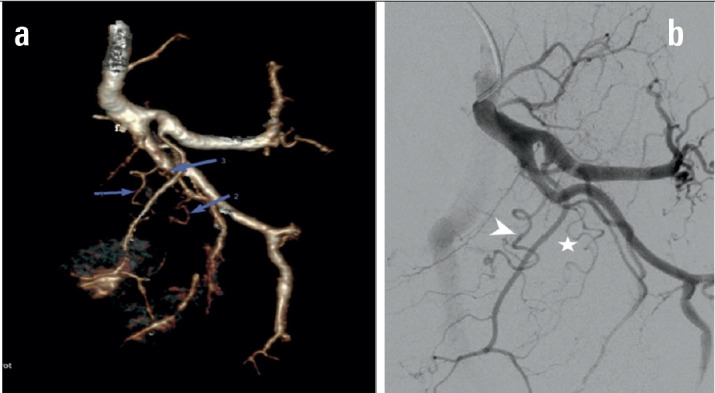

Objective: The study aimed to describe the anatomy and imaging findings of the prostatic artery (PAs) on 3D rendering dual-energy multi-sequence computed tomography (DECT) in patients with symptomatic benign prostatic hypertrophy (BPH) treated by prostatic artery embolisation (PAE).

Methods: The study was conducted on 64 patients with BPH who underwent DECT scans with 3D rendering of the pelvic artery before intervention from August 2022 to November 2023. The PAs were independently evaluated for each side, focusing on the number of branches, origin, tortuosity, atherosclerotic plaque, and anastomoses with adjacent arteries.

Results: Among 128 pelvic sides where the PAs can be observed, the rate of finding 01 prostate artery on each side was high (96.1%), and the rate of 02 prostate arteries on each side was rare (3.9%). In 133 prostatic arteries, the most common type of prostatic artery according to origin is type I (29.6%), followed by type III (24.6%). The atherosclerotic prostatic artery rate is 24.6%, and the average diameter is 1.5±0.4 mm. The tortuosity prostate artery accounted for 74.6%. The anastomosis to the contralateral prostatic artery rate is 48.4%, followed by the penis and rectum anastomoses.

Conclusion: PAs have abundant original varies between the left and right sides and between patient to patient. The most common form arises from the internal pudendal artery.